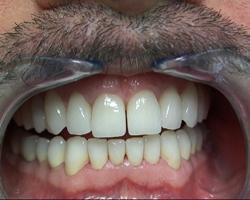

Vue finale

Avant.

Après avec augmentation de la DVO de 6 mm.